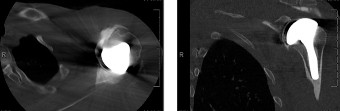

This classification was originally based on CT imaging but is now applied to MRI imaging and uses sagittal oblique views at the most lateral slice in which the scapular spine is continuous with the scapular body. There are five categories that range from stage 0 to stage 4. A classification of stage 0 is normal, stage 1 is some fatty streaks, stage 2 is more muscle than fat, stage 3 is equal amounts of fat and muscle, and stage 4 is more fat than muscle. This patient’s rotator cuff tear involves the supraspinatus and infraspinatus, and both have atrophied to the point of having equal amounts of fat and muscle, giving her tear a Goutallier classification of stage 3 (see Table 2–2 and Fig. 2–18). As a general rule, if there is stage 3 or 4 fatty atrophy, rotator cuff repair will not be successful and a reverse total shoulder or tendon transfer would be a better operation.

Figure 2–18_Three different patients showing different stages of fatty degeneration with Goutallier stages. Higher stages are predictive of worse outcomes after rotator cuff repair. SS, supraspinatus; IS, infraspinatus; TM, teres minor; Sub, subscapularis. (From Kuzel BR, Grindel S, Papandrea R, Ziegler D. Fatty infiltration and rotator cuff atrophy. _J Am Acad Orthop Surg. 2013;21(10):613–623.)